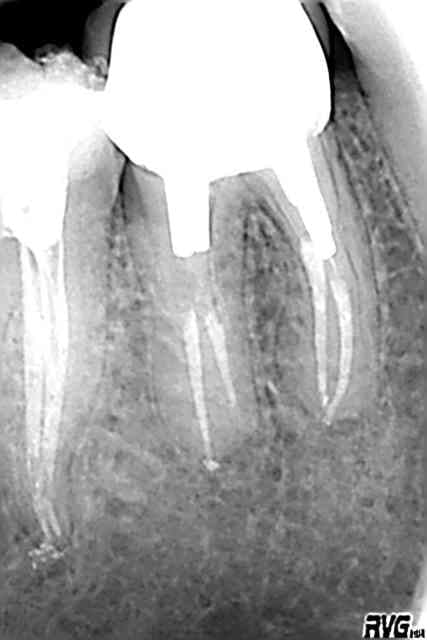

je précise que la radio jointe c'est un de ses cas.

et pour le plaisir des yeux, quelques cas qu'il m'a envoyé...